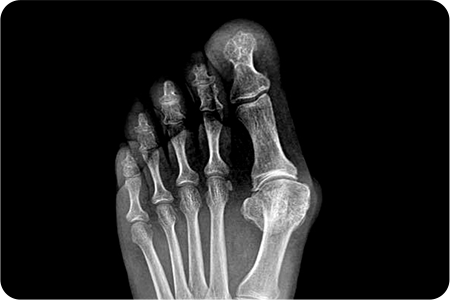

중증도의 심한 통증

20~40도의 변형

발 20도 이하의 변형 이미지

40도 이상의 변형